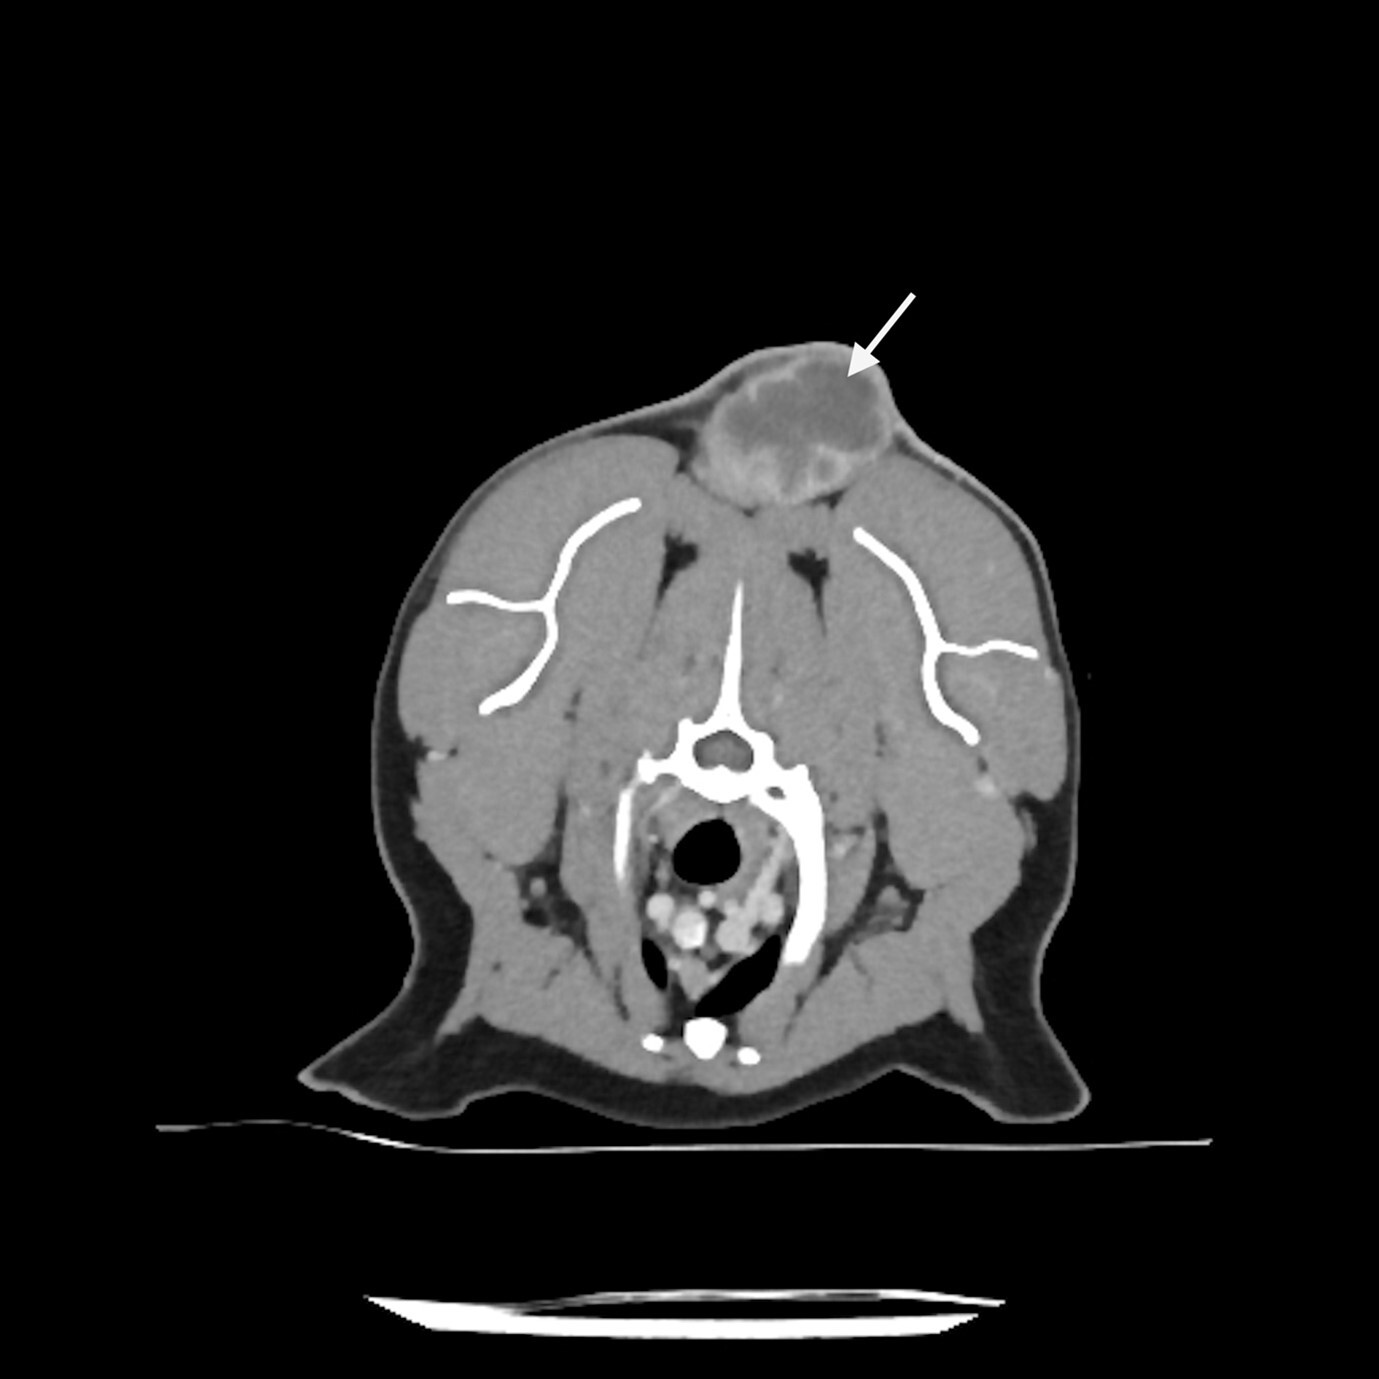

FISSs typically have long finger-like projections lateral and deep to the main mass and can also have smaller “satellite” nodules peripheral to the primary tumour. Contrast-enhanced computed tomography (CT), or less commonly MRI, helps visualise these and aid surgical planning (Figure 1). For interscapular ISS, post-contrast CT scans should be performed with the forelimbs extended both cranially and caudally along the body, as this allows a better understanding of the relationship between the tumour and adjacent tissue (Longo et al., 2018). As the surgical dose for ISSs can be large, imaging should include the abdominal and thoracic cavities to screen for comorbidities that may preclude a more invasive treatment approach.

Currently, it is advised to resect ISSs with 5cm lateral margins and two uninvolved fascial planes as the deep margin, although this can be reduced to 3cm lateral margins if based on CT imaging. This results in complete excision in 95 to 97 percent of cases compared to 50 percent when only 3cm lateral margins (based on palpation) are obtained (Davidson et al., 1997; Hershey et al., 2000; Phelps et al., 2011; Romanelli et al., 2008). For ISSs in the interscapular region, surgery often involves the excision of dorsal spinous processes and the tips of the scapula, whereas body wall resection or amputation are usually required for ISSs of the flank and extremities, respectively (Figure 2).